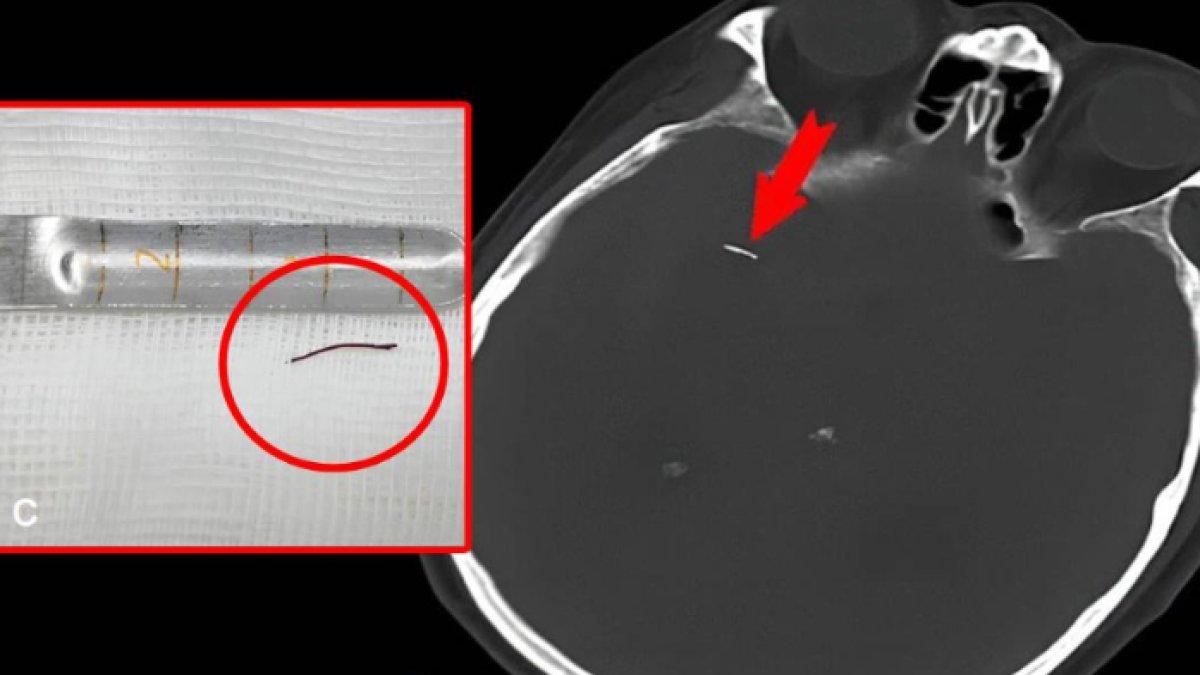

Pasien tersebut, seorang pria berusia 74 tahun yang tinggal di Provinsi Sichuan, Tiongkok, hasil pemindaiannya menemukan "jarum emas" sepanjang 1,3 cm di arteri serebral di belakang mata.

Benda asing menyebabkan pendarahan internal.

Jarum bisa patah selama akupunktur. Kemudian bergerak ke arteri di belakang mata.

Pasien menjalani kraniotomi untuk melepas jarum.

Pertama, dokter harus memotong sebagian tengkorak untuk mendapatkan akses ke otak.

Mereka kemudian menggunakan mikroskop bedah untuk mencabut jarum tersebut.